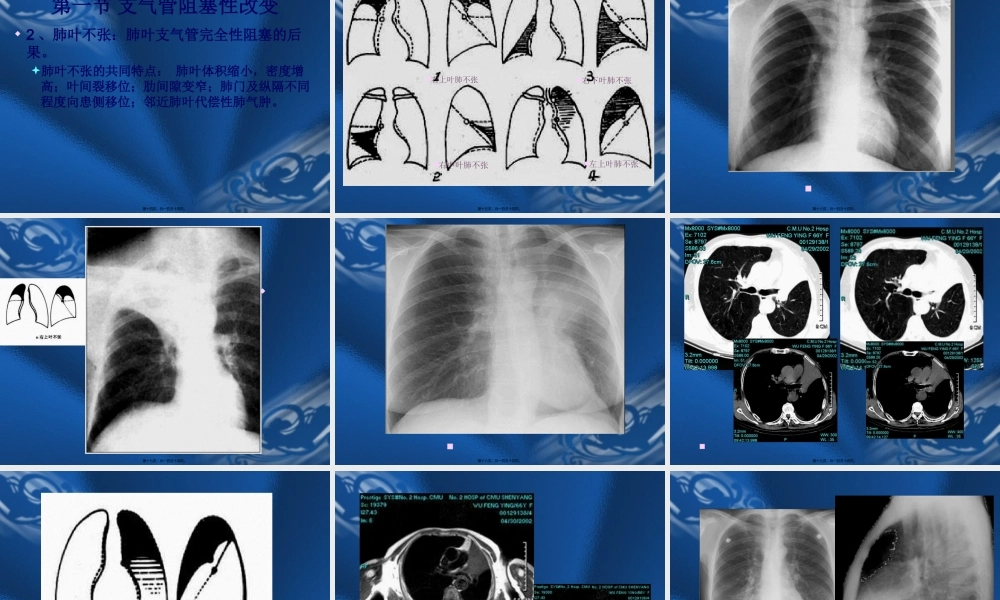

呼吸系统根本病变的影像学表现第一页,共一百五十四页。第二页,共一百五十四页。第一节支气管阻塞性改变第三页,共一百五十四页。第一节支气管阻塞性改变一、阻塞型肺气肿(obstructiveemphysema)1、两肺阻塞性肺气肿:见于慢支及支气管哮喘。影像表现:肺野透过度增加,与呼吸时相关系不大;肺纹理稀疏变细,可见肺大泡。横膈低平,活动度减低;胸廓呈桶状,肋间隙增宽;心影狭长呈垂位心型,心后间隙增宽。第四页,共一百五十四页。第一节支气管阻塞性改变2、局限性阻塞性肺气肿一侧性肺气肿:一叶性肺气肿:影像表现:肺内表现同上;纵隔向健侧移位或移位不明显。气管内异物可表现为纵隔摆动。支气管断层或造影有利于诊断。第五页,共一百五十四页。第六页,共一百五十四页。第七页,共一百五十四页。肺泡肺泡壁终末细支气管第八页,共一百五十四页。小叶中心型肺气肿全小叶型肺气肿第九页,共一百五十四页。第十页,共一百五十四页。阻塞性细支气管炎(BronchiolitisObliterans)指细支气管发炎的病变,导致支气管壁纤维化以及管腔阻塞。第十一页,共一百五十四页。阻塞性细支气管炎(BronchiolitisObliterans)呈现—马赛克灌注,磨玻璃密度区肺血管增粗。第十二页,共一百五十四页。第一节支气管阻塞性改变二、阻塞性肺不张〔obstructiveatelectasis〕1、一侧性肺不张:一侧主支气管完全性阻塞的后果。影像表现:患侧肺野均匀一致密度增高影;胸廓塌陷,肋间隙变窄;纵隔向患侧移位;患侧膈肌升高;健侧代偿性肺气肿。第十三页,共一百五十四页。第一节支气管阻塞性改变2、肺叶不张:肺叶支气管完全性阻塞的后果。肺叶不张的共同特点:肺叶体积缩小,密度增高;叶间裂移位;肋间隙变窄;肺门及纵隔不同程度向患侧移位;邻近肺叶代偿性肺气肿。第十四页,共一百五十四页。右上叶肺不张右下叶肺不张左上叶肺不张右中叶肺不张第十五页,共一百五十四页。第十六页,共一百五十四页。第十七页,共一百五十四页。第十八页,共一百五十四页。第十九页,共一百五十四页。第二十页,共一百五十四页。第二十一页,共一百五十四页。第二十二页,共一百五十四页。第二十三页,共一百五十四页。第二十四页,共一百五十四页。第一节支气管阻塞性改变3、肺段不张或肺小叶不张:表现为三角形致密影,基底向外,尖端指向肺门,肺段体积缩小。小叶不张多表现...